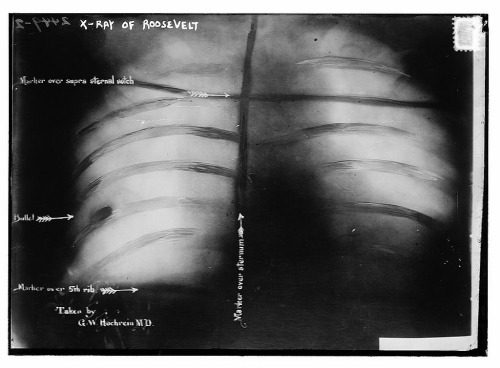

John Schrank – atentátnik a jeho revolver Snímok hrude

Snímok hrude